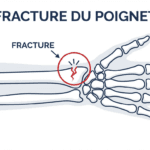

Entorse, luxation ou fracture

Un traumatisme direct, comme une chute sur la main, peut provoquer :

- une entorse : étirement ou rupture d’un ligament,

- une luxation : déplacement d’un os,

- une fracture du scaphoïde ou du radius distal.

Ces blessures nécessitent une prise en charge rapide pour éviter des séquelles.